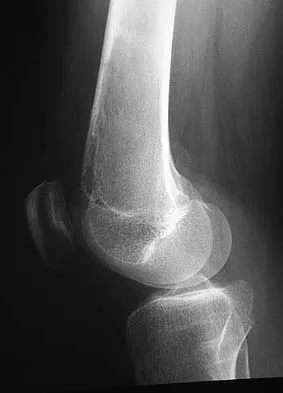

A 15-year-old boy reports leg pain after being tackled during football practice. Radiographs and a CT scan are shown in Figures 46a through 46c. The patient has a pathologic fracture through what underlying lesion?

Explanation

The images show a lobulated, eccentric, well-marginated lesion that is typical of a nonossifying fibroma. The lesion is slightly expansile, and the CT scan findings show that the lesion is very well marginated and the cortex is disrupted, which is a common finding. None of the characteristics of this lesion is aggressive in nature. Menendez LR (ed): Orthopaedic Knowledge Update: Musculoskeletal Tumors. Rosemont, IL, American Academy of Orthopaedic Surgeons, 2002, pp 69-75.